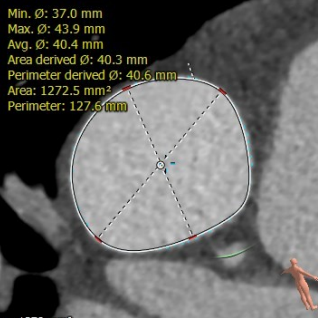

患者,男,32岁,入院超声提示为“肺动脉重度关闭不全并轻度狭窄,右心增大” ,术前影像学重建显示提示患者肺动脉干明显增宽,内径约38-45mm,瓣膜的固定成为了手术难点。经过术前多团队的缜密分析讨论,传统开胸手术建立体外循环对患者创伤大、手术操作复杂;该患者肺动脉明显扩张,经股静脉介入肺动脉瓣无法提供合适锚定位置;遂决定采用佰仁医疗Salus介入肺动脉瓣来解决这一问题,该瓣膜采用“哑铃状”镍钛合金记忆金属支架,优越的径向支撑力可锚定于病变部位,适用于可直接放瓣的肺动脉瓣反流/狭窄患者;通过独有的经胸介入方式,对于肺动脉解剖结构复杂、无法提供介入瓣膜合适锚定位置的患者,可同期行肺动脉成形术+介入肺动脉瓣植入术,达到理想的治疗效果,适用范围更广。

肺动脉内径测量